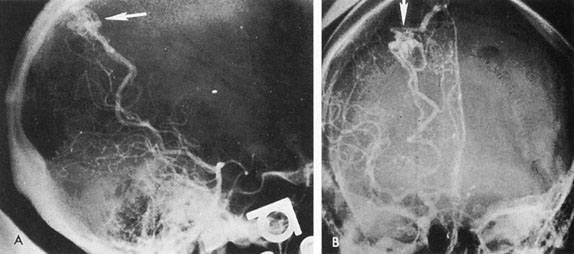

Fig. 6. Fusiform basilar dilation. A: Lateral projection vertebral arteriogram showing a widened basilar artery (arrow) projecting beyond level of dorsum sellae. B: Anteroposterior projection showing a widened and tortuous basilar artery.

Tortuous or redundant basilar arteries are not uncommon in the older age group. Occasionally, gross dilation or ectasia develops so that the basilar artery acts as a mass in the posterior fossa. This phenomenon produces signs of low-pressure hydrocephalus, cranial nerve palsies, and long tract and sensory signs and may even simulate a cerebellopontine angle tumor or tumor at the foramen magnum.58 It is possible to diagnose such lesions with CT59 or MRI60 but angiography is definitive (Fig. 6). The association of insidious multiple cranial nerve palsies and long tract signs referable to a brainstem level, in an elderly patient with evidence of atherosclerosis, should make fusiform basilar artery dilation a diagnostic consideration.